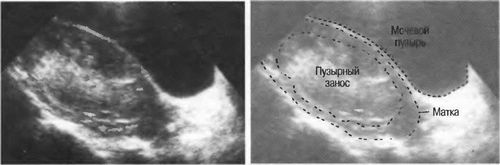

Проблеми на етапі запліднення можуть стати причиною серйозних ускладнень. Одним з найбільш небезпечних є міхурово занесення. Він розвивається внаслідок запліднення дефектної яйцеклітини, яка не має хромосом або ж запліднення двома сперматозоїдами. У першому випадку в зиготі подвоюється батьківський набір хромосом, але вона все одно є нежиттєздатною. У другому зигота матиме надто великий обсяг генетичного матеріалу, що також не дозволить їй нормально розвиватися.

Виявляють цю патологію зазвичай на 11-25 тижні вагітності, після чого проводять хірургічне лікування. Приблизно в 20% випадків міхурово занесення перероджується в злоякісне новоутворення і викликає метастатичні трофобластичних пухлини. Зустрічається це ускладнення рідко - в 0,02-0,8% випадків.